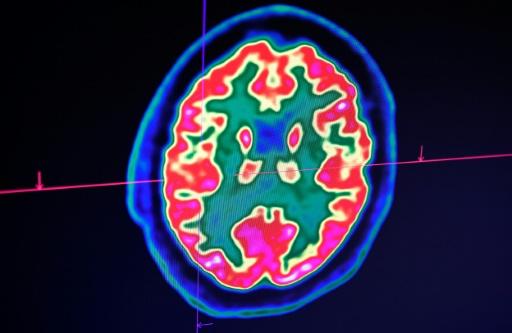

E um artigo do New England Journal of Medicine, a revista médica americana de maior prestígio, destaca que médicos franceses estudaram 58 pacientes com coronavírus e comprovaram que metade deles estavam desorientados ou agitados. Exames de imagens do cérebro mostraram possíveis inflamações.

Este paciente se mostrou desorientado, sofreu convulsões e o exame de imagem do cérebro revelou inflamações. Mas os cientistas preferem a cautela, pois trata-se de um único caso conhecido até o momento e que os exames para detectar o vírus no líquido cefalorraquidiano ainda não foram validados.